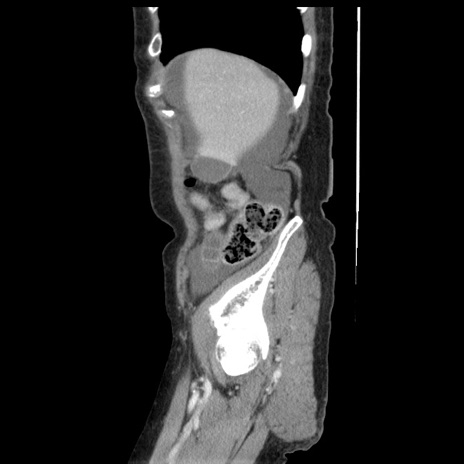

冠状断像